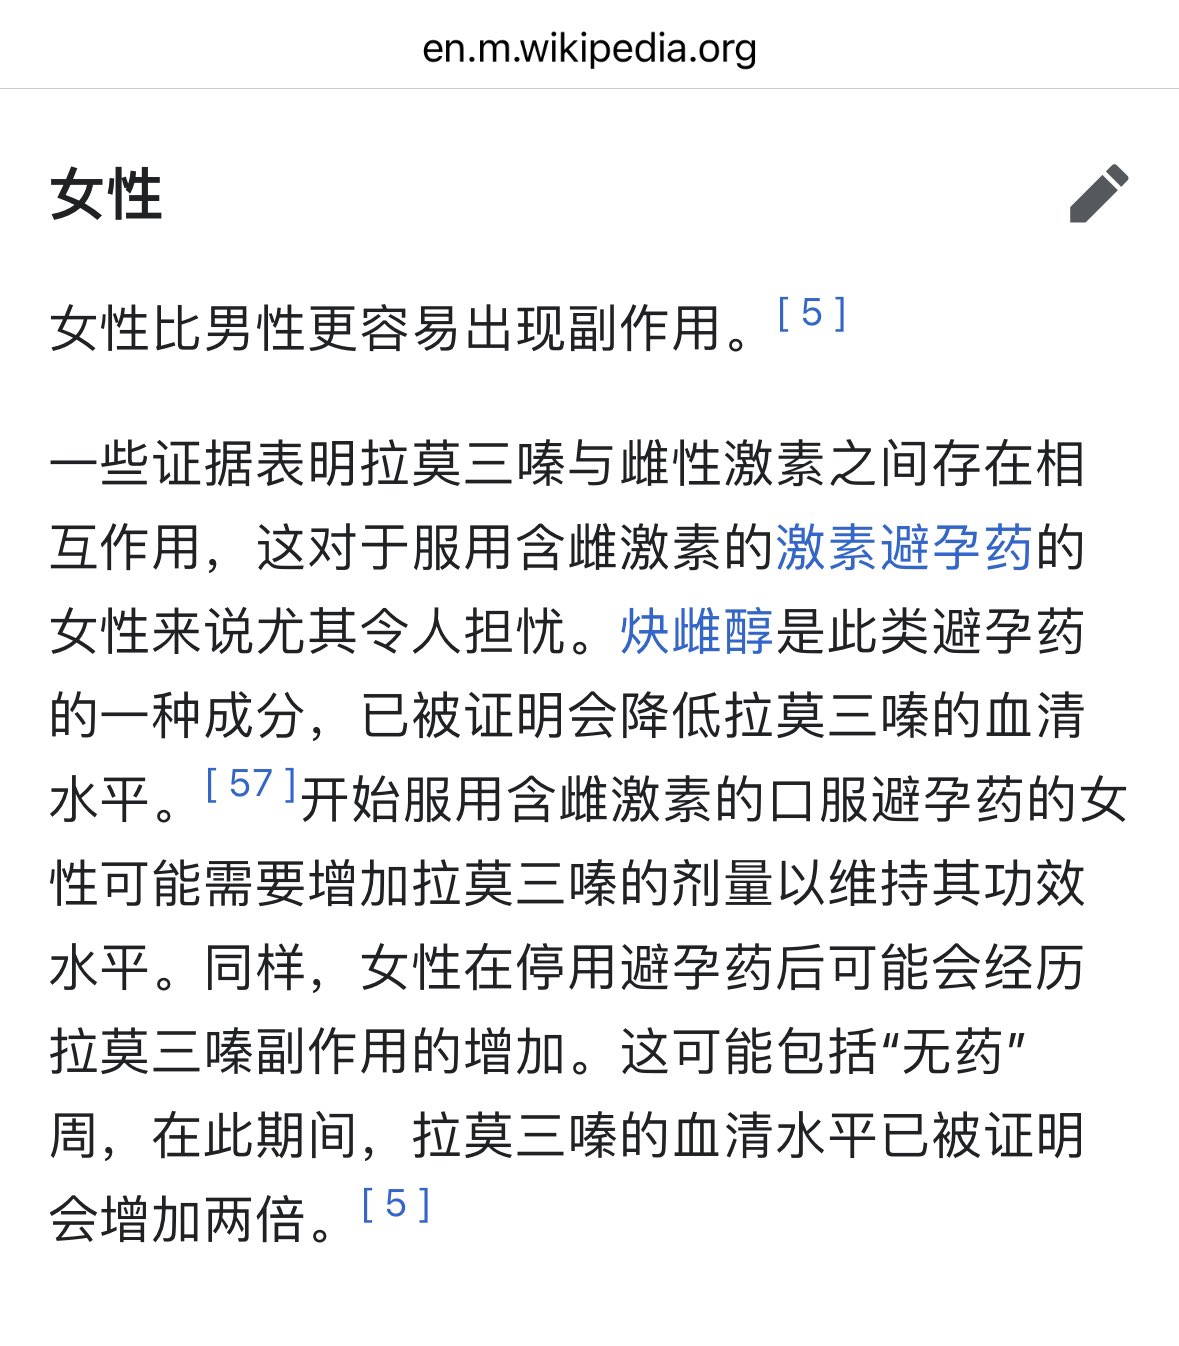

首先,从定义上讲,“反解离(anti-dissociative)”并不是一个标准的医学术语或者广泛认同的药理学分类。在正规资料,比如医学文献、维基百科、精神药理学教科书中,目前并没有“反解离药物”这个正式概念。

看上去像是为了描述某类特定效应而创造的术语(可能是nmda受体活性增强),用来对抗因NMDA受体拮抗剂(比如氯胺酮、DXM、PCP等)引发的解离体验(dissociation)。

那么更常见的是将其归入认知增强剂(cognitive enhancers),特别是改善认知连接性(connectivity)和现实感知(reality testing)的类型。

但其实在药理学上,单纯用“受体激动剂”来逆转“受体拮抗剂”的效应,有时会导致过度激活。

对于NMDA受体而言,过强的NMDA活化本身就与兴奋性毒性(excitotoxicity)和精神病样症状(psychotomimetic effects)有关,比如谷氨酸风暴可以引发严重的焦虑、妄想、乃至癫痫。

也就是说,简单地“激动-解除拮抗”在中枢神经系统是很危险的做法,尤其是对于易感个体(如有精神分裂素质的人)。

科学的处理方式一般是通过更细致的调节,比如微调NMDA/AMPA平衡、调节其他辅助途径(如GABA、5-HT、mGluR受体),而不是简单粗暴地用“NMDA增强剂”去顶回去。

而临床处理药物中毒中,其实医生更常用的做法是保守、支持性的治疗,比如补液,促进代谢,必要时镇静,以及监测生命体征防治并发症。

药物拮抗与受体激动之间,往往牵扯到的是复杂的适应性变化(receptor upregulation/downregulation),

不是简单的“给多一点刺激就能抵消”的关系